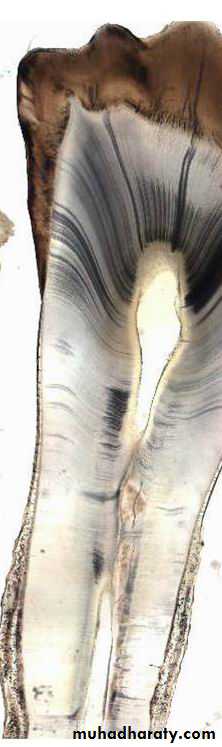

How To Study The Histological Structures Of Dentin

Ground section (inorganic part)

Decalcified section (Organic part)